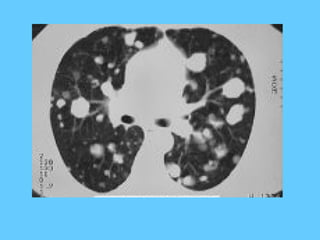

Miliary tuberculosis

Tuberculosis